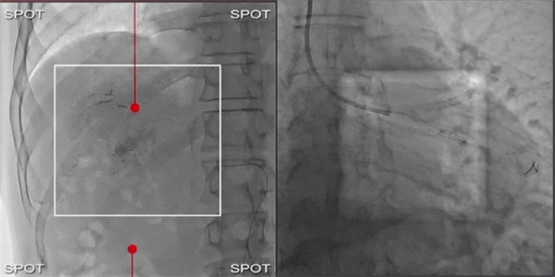

结合AI智能工作流平台,医生可床旁操作,技师可同步准备,患者无需频繁移动,实现智慧协作与高效诊疗。此外,Sky+还配备智能微剂量技术和全临床智能解决方案。特色的靶向透视(SPOT Fluoro /左图)和双能量透视(SPOT ROI/右图)模式,可提升导丝和导管的可视性,从而减少每次操作的辐射剂量。辐射区域可独立调整,确保仅暴露执行手术所需的最小范围,无需移动患者或调整系统位置,有效降低患者及医护的辐射暴露。

中国香港Queen Elizabeth Hospital介入心脏病学主任Christopher Zeitz教授表示:“Spot ROI系统有助于降低患者及医护人员的辐射剂量。该系统通过在射束中引入带孔径的滤光片,使我们在治疗部位维持所需图像质量的同时,仍能清晰观察导管尖端和导丝尖端的周边视野,且辐射剂量降低65-85%。”